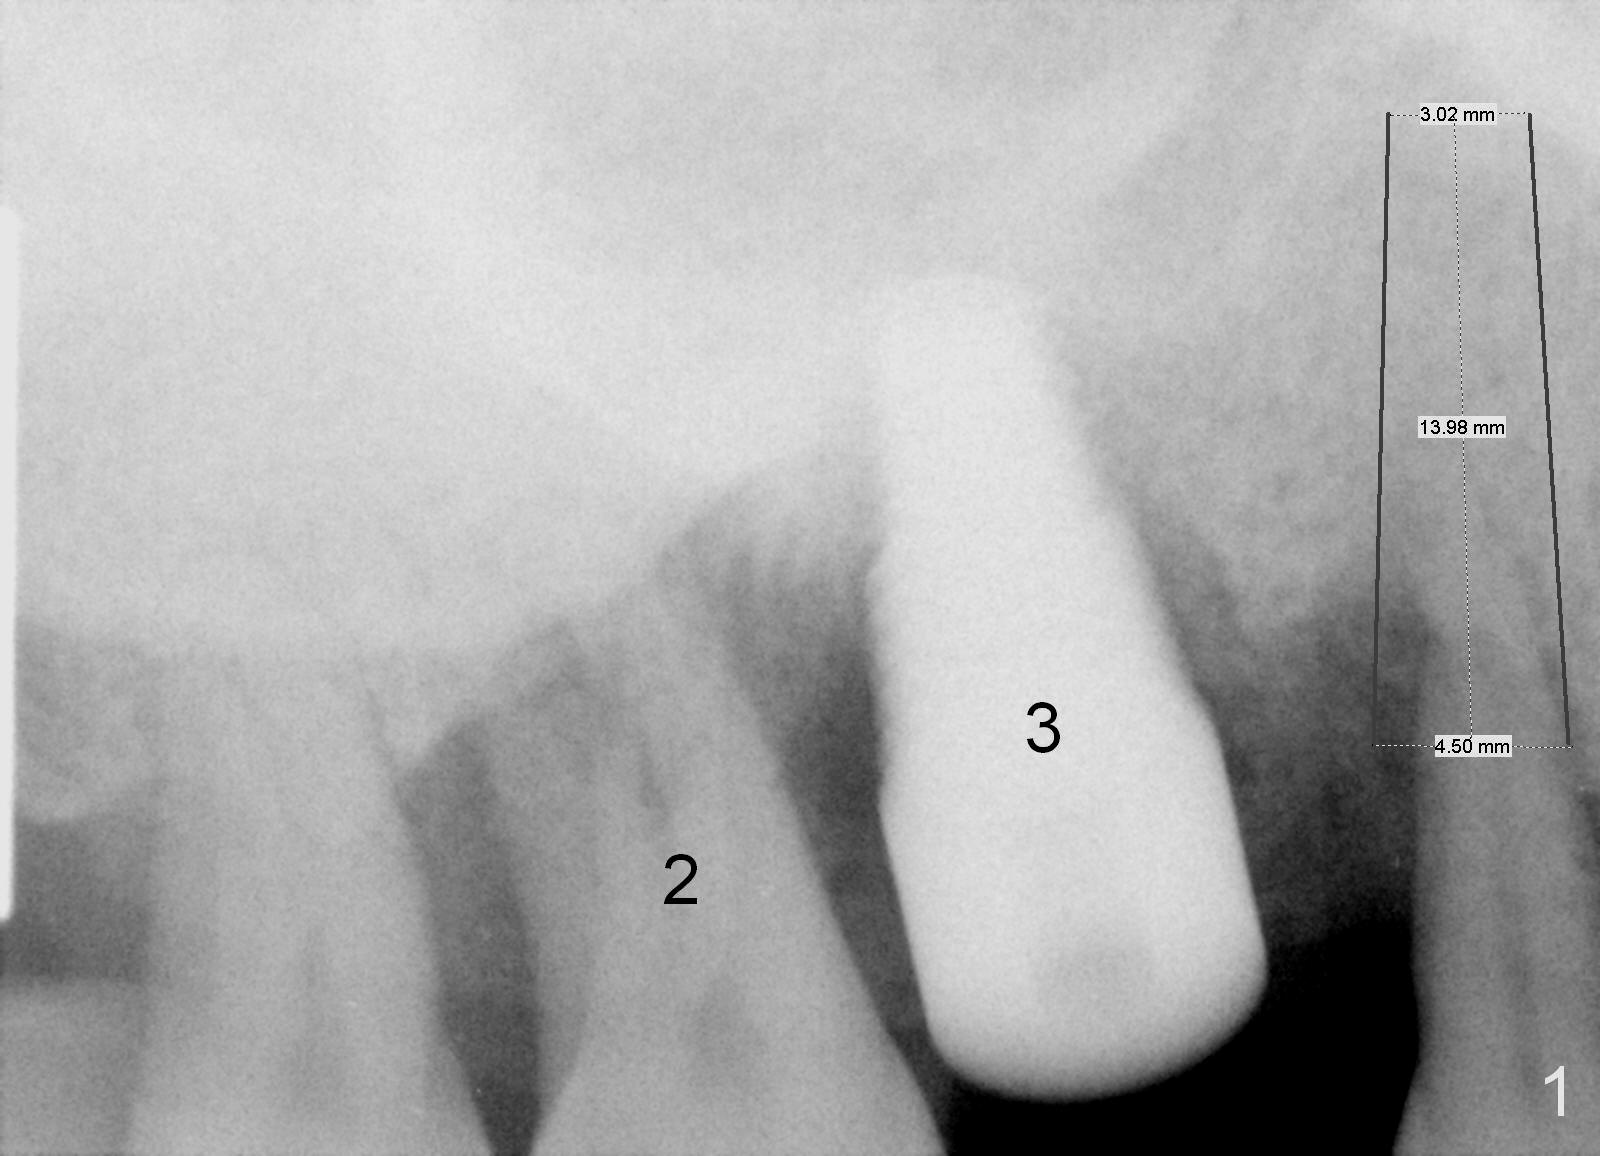

A 46-year-old man has severe chronic periodontitis associated with bruxism.  The teeth #3 and 2 have been replaced with immediate implants (Fig.1,2).  Now the tooth 4 should be treated in the same manner.  Since there is sufficient bone with uneven bone resorption, a long bone-level implant is needed for primary stability (>13 mm).  Cuff length of the tissue-level implant is fixed, while there are different lengths of the cuff associated with bone-level implants.  Metronidazole is the antibiotic to be used for socket disinfection.  Intraop PA should be taken with the pilot drill or a parallel pin to avoid invading the neighboring root or implant.  Abundant bone graft is required (circles, Fig.2).